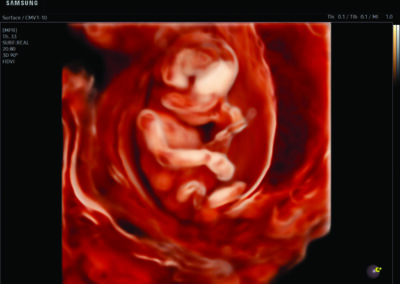

Comprehensive, advanced and expert MFM care for high-risk pregnancies